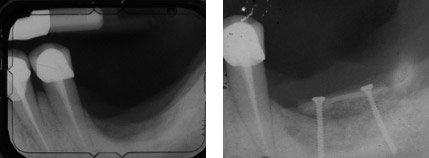

Techniques d’augmentation osseuse intra-sinusienne